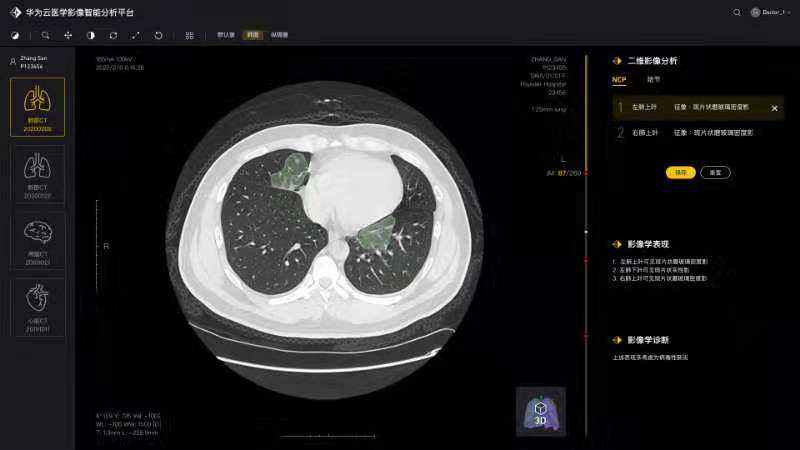

将论文写在祖国的大地上,加快加强疫情防控科研攻关,服务一线疫情防控救治——疫情发生以来,由学院白翔、许永超等老师负责的bat365在线登录入口—华为智能创新实验室积极发挥自身优势,组织团队师生争分夺秒抓紧开展高质量科研攻关,与附属协和医院放射科、华为云、篮网科技等团队共同研发出一套基于人工智能技术的面向新冠肺炎肺部CT影像量化分析系统。2月29日下午,中共中央政治局委员、国务院副总理孙春兰率中央指导组来校考察疫情防控科研攻关情况,许永超副教授当场向孙副总理介绍了研发推出该系统的工作及成果。该系统可以辅助医生更高效地区分新冠肺炎的早期、进展期与重症期,有利于早期筛查与防控。同时,对于确诊病人,基于对多次复查影像数据的量化分析,医生能够有效评估病情进展及用药疗效等情况。目前该系统已在全国几十家医院使用,日均调用量3000多次。孙春兰肯定了研究团队所开发系统的精确性,可以辅助医生定量分析,大幅提升效率,缓解影像医生的压力。她非常关注该系统的落地应用情况,特别是在湖北省、武汉市的应用,鼓励团队结合CT影像与核酸试剂等信息,进行更为精准的新冠肺炎诊断。